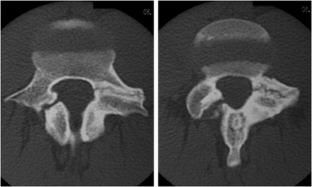

Atypical, unusual, and misleading imaging presentations of spondylolysis

Although lumbar spondylolysis is a widely known and easily recognizable condition in its typical presentation, there are some less well-known forms that may occasionally be challenging and/or demand special attention on imaging. Examples include: acute and/or incomplete lesions; unilateral defects; lesions at unusual levels (cervical, upper lumbar, and multi-level spondylolyses); iatrogenic lesions; non-isthmic spondylolysis; and spondylolysis related to underlying diseases. In addition to their atypical, uncommon or confusing imaging presentations, these forms of spondylolysis are far rarer than the classic type and have been described, to a great extent, in the surgical literature, thus reducing the awareness of radiologists about them and raising the potential for misdiagnosis and inadequate treatment. In this review the authors address these special manifestations of spondylolysis, stressing the more important features to be considered in the differential diagnosis and the impact of a precise diagnosis of spondylolysis on the patient’s care.